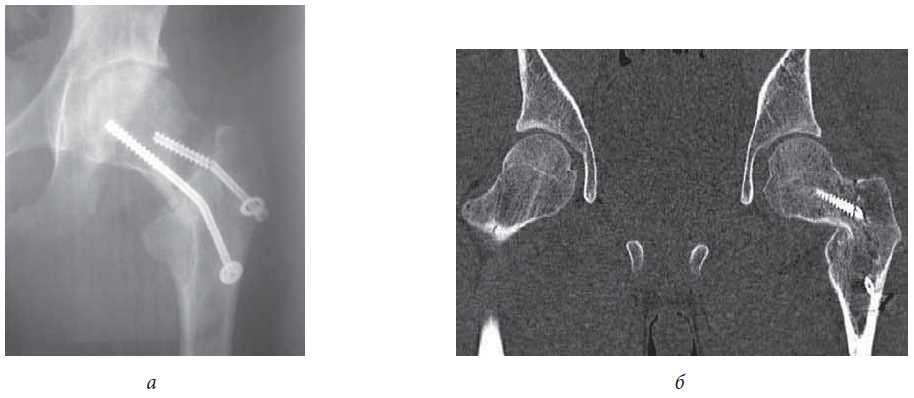

The average score on the patient self-evaluation scale after surgery was 0.08 (95% CI 0.04–0.13). Cannulated screws were not removed from any patient since such a second surgical intervention would be highly traumatic (requiring full surgical access to the lateral surface of the femur greater trochanter). Total endoprosthesis replacement of the hip joint was not required in any case. Long-term treatment outcomes are shown in Fig. 8, 9.

Fig. 8. Patient M., 15 years old. The result of surgical treatment after 5 years: a - X-ray of the hip joints in a direct projection: the absence of signs of aseptic necrosis of the head of the femur, the correct position of the metal structures; b - X-ray of the hip joints in the projection on Lauenstein: absence of signs of aseptic necrosis of the femoral head, correct position of the metal structures, absence of secondary displacement; in, г - a functional result in 6 years - restrictions and a painful syndrome are not present

Fig. 9. Patient M., 21 years old. The result of surgical treatment after 7 years: a - X-ray of the hip joints in a direct projection: the absence of signs of aseptic necrosis, secondary changes in the proximal part in the form of deformation as cam-impingement; b - X-ray of the hip joints in the projection on Lauenstein: absence of signs of aseptic necrosis, an increase in off set and angle α (cam-impingement); c, d - functional result 7 years after repeated surgical treatment: minimal limitation of lead in the left hip joint, no pain syndrome